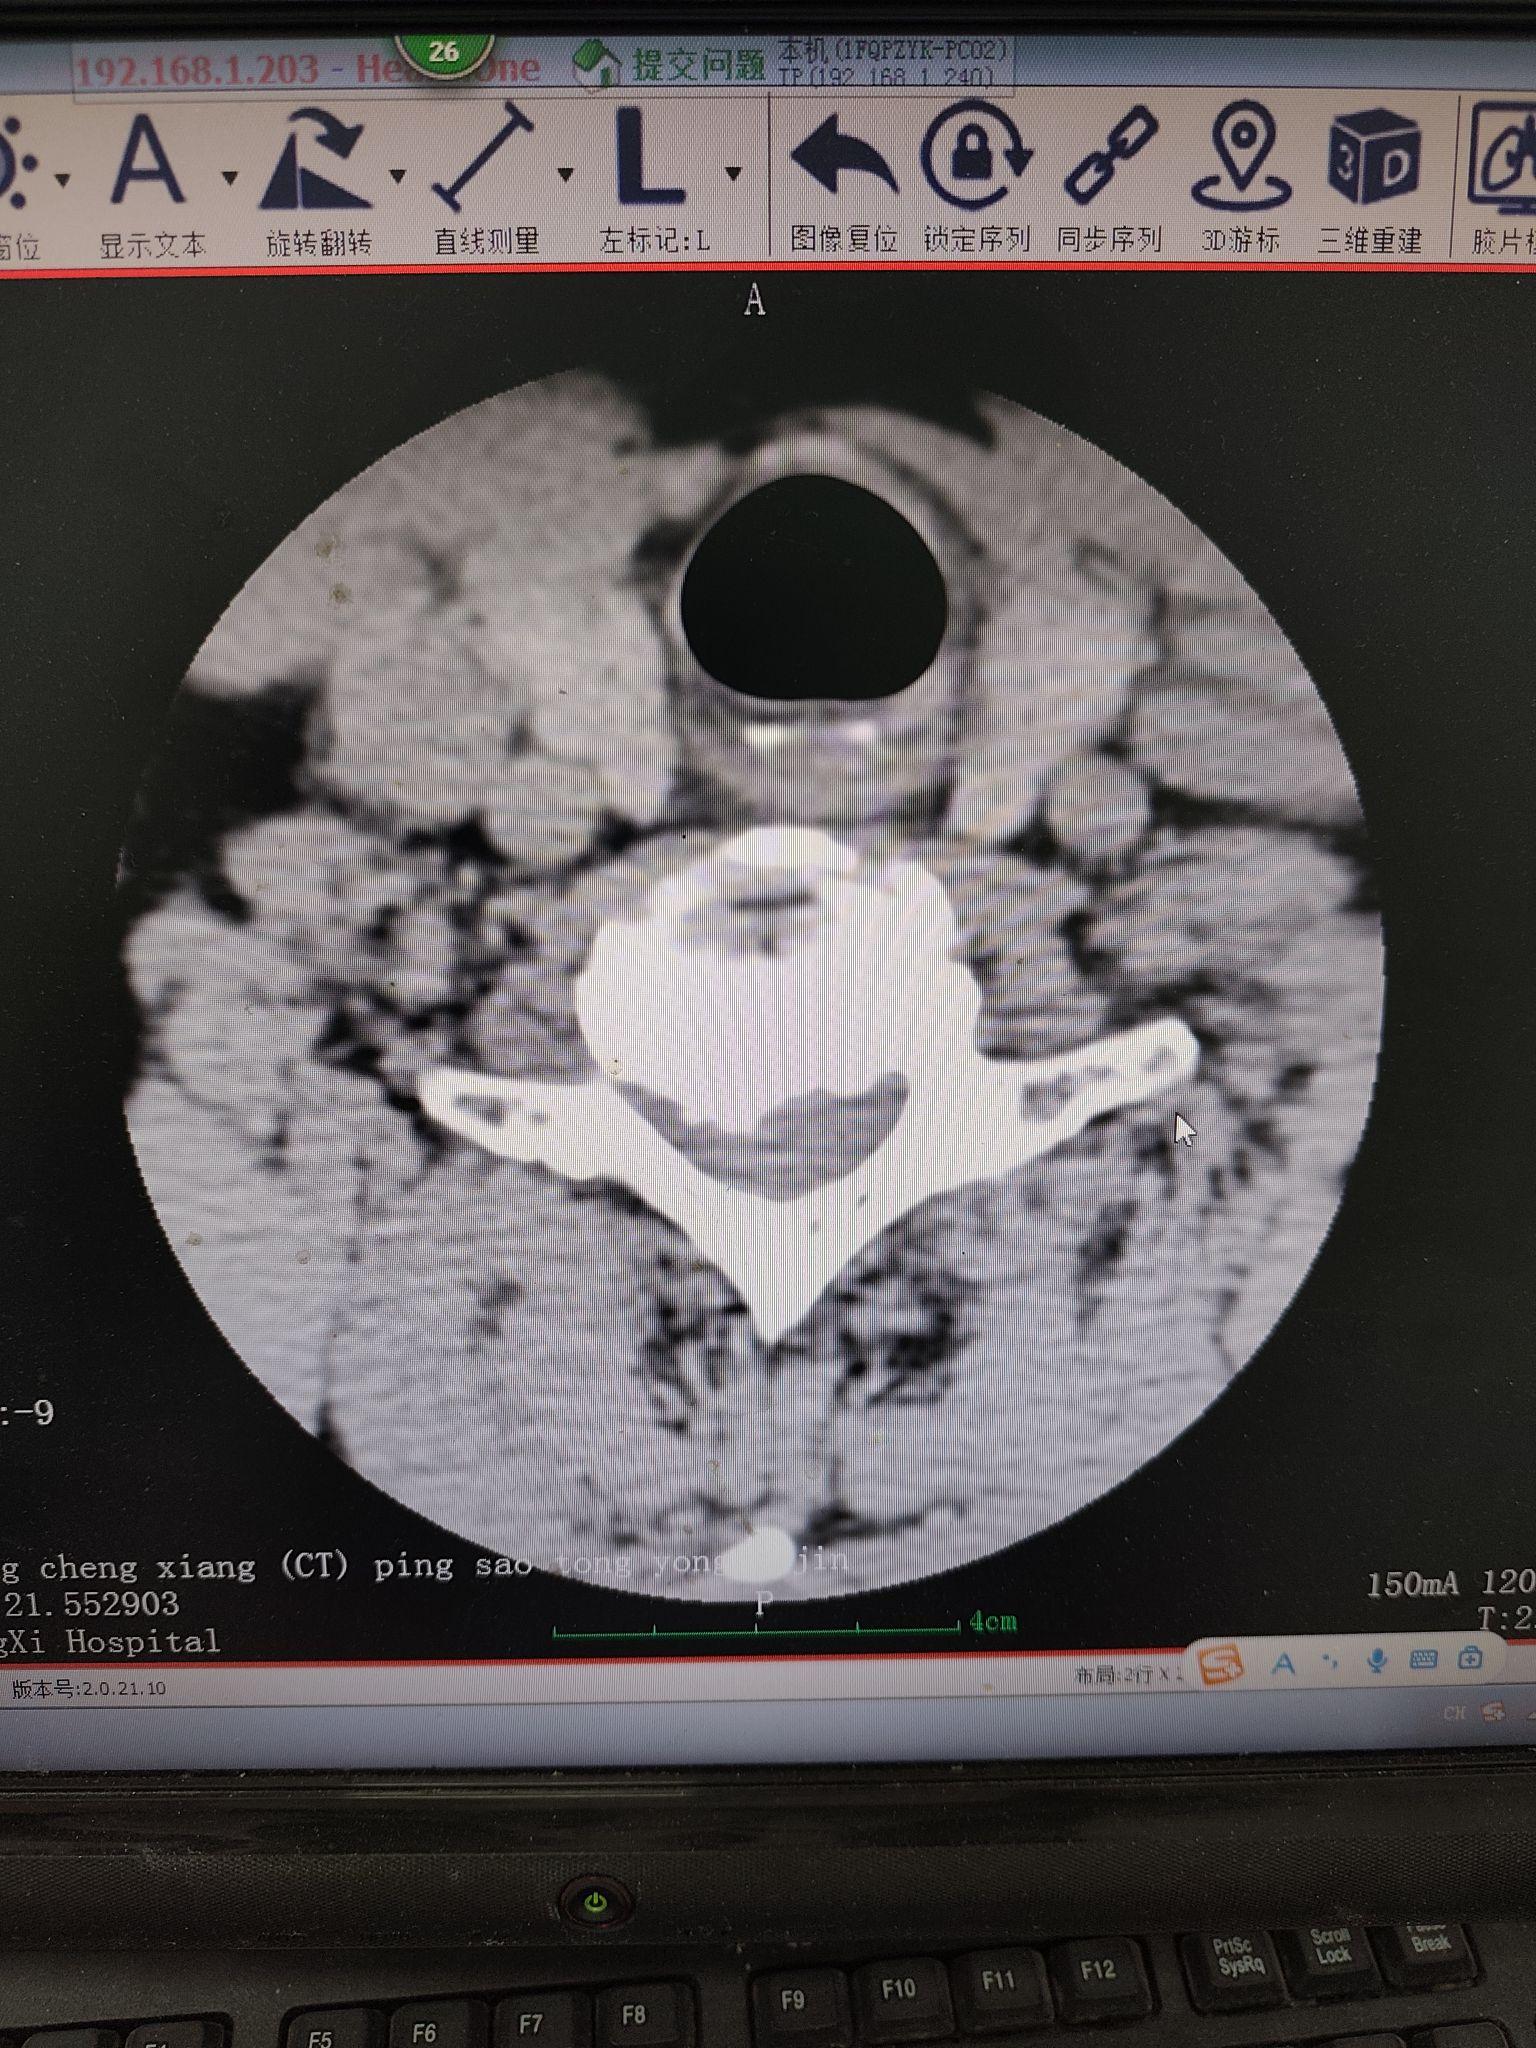

颈椎间盘突出,椎管狭窄